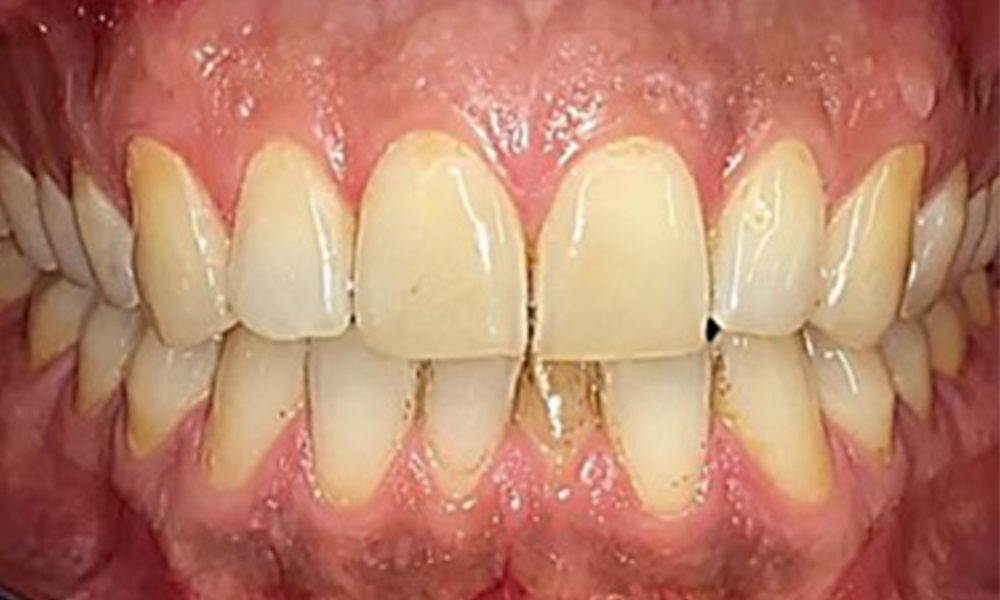

Observații la nivel dentar

Pacientul prezintă o dentiție completă, cu 28 de dinți. Se remarcă eroziuni și atriții. (Fig. 4, Fig. 5). Datorită bruxismului, timp de mulți ani, pacientul a purtat gutieră pe timp de noapte. Eroziunile sunt cauzate de consumul prelungit de băuturi izotonice. Nu au fost observate pierderi osoase de natură parodontală sau carii active.